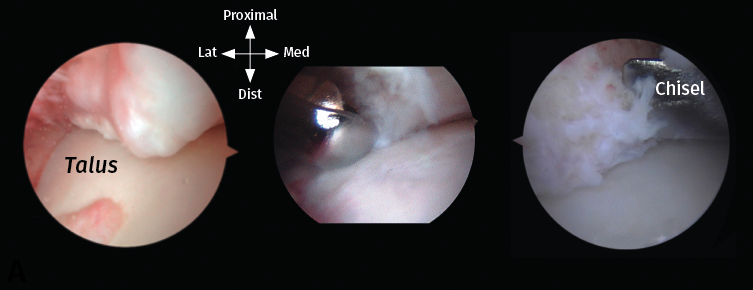

Se reseca en primer lugar el tejido sinovial con un terminal motorizado sinoviotomo del mayor diámetro disponible y con su abertura siempre dirigida hacia el hueso. Los osteofitos se resecan mediante un terminal motorizado de tipo bola de 4 mm (Figura 5). Se facilita la identificación y la resección de estos posicionando el tobillo en flexión dorsal, lo que impide que la cápsula articular anterior los oculte. Además, el astrágalo y su capa articular quedan así protegidos bajo la tibia de posibles daños iatrogénicos. El contorno anterior de la tibia distal se identifica resecando el tejido sinovial que lo cubre; seguidamente, se reseca el osteofito y esta resección se amplía extendiéndola al propio maléolo interno hasta liberar completamente el pinzamiento. La exposición se puede mejorar llevando el tobillo a una posición de flexión dorsal forzada; con esta maniobra se aumenta el área de trabajo del receso capsular anterior.

Figura 5. Descripción del procedimiento quirúrgico paso a paso. A: un osteofito se encuentra a nivel anterior de la tibia distal; B: el tejido sinovial se reseca con un sinoviotomo de ventana grande con la abertura siempre dirigida hacia el hueso; C: los osteofitos se escinden con un sinoviotomo o fresa artroscópica de 4 mm, o con un pequeño escoplo.